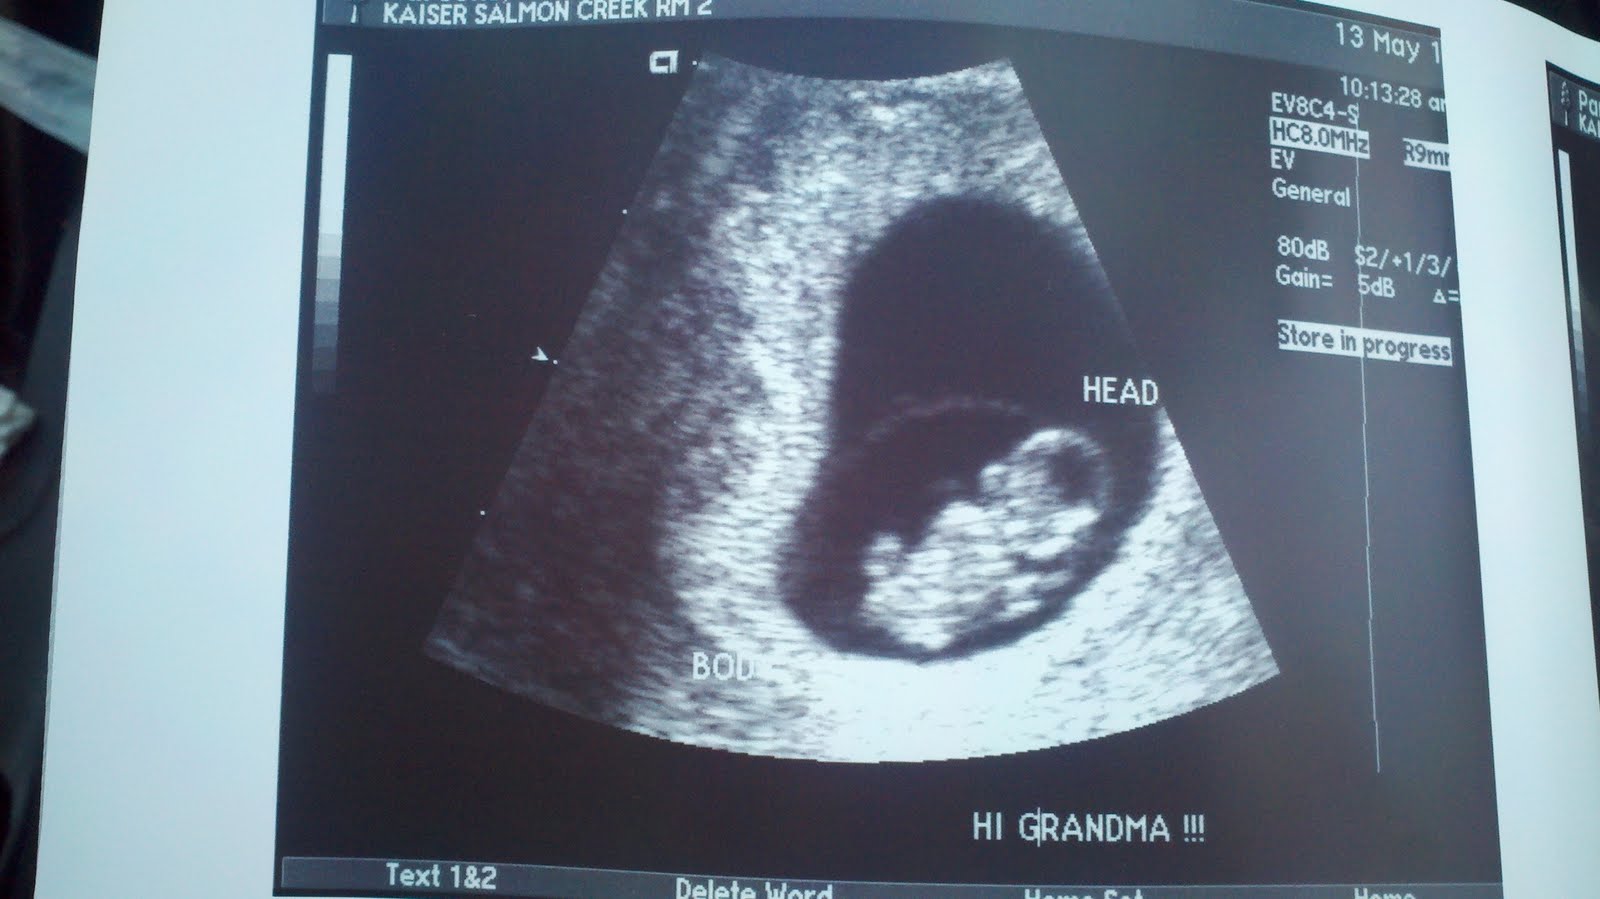

На 7 акушерских неделях беременности плод продолжает активно расти и формироваться. Фотографии узи в этот период могут показать уже сформировавшиеся основные органы и системы плода, такие как сердце, печень, почки и другие.

Процесс развития плода на 7 акушерских неделях может быть уникальным для каждой беременной женщины, поэтому фотографии узи помогут вам лучше понять и оценить этот важный этап.